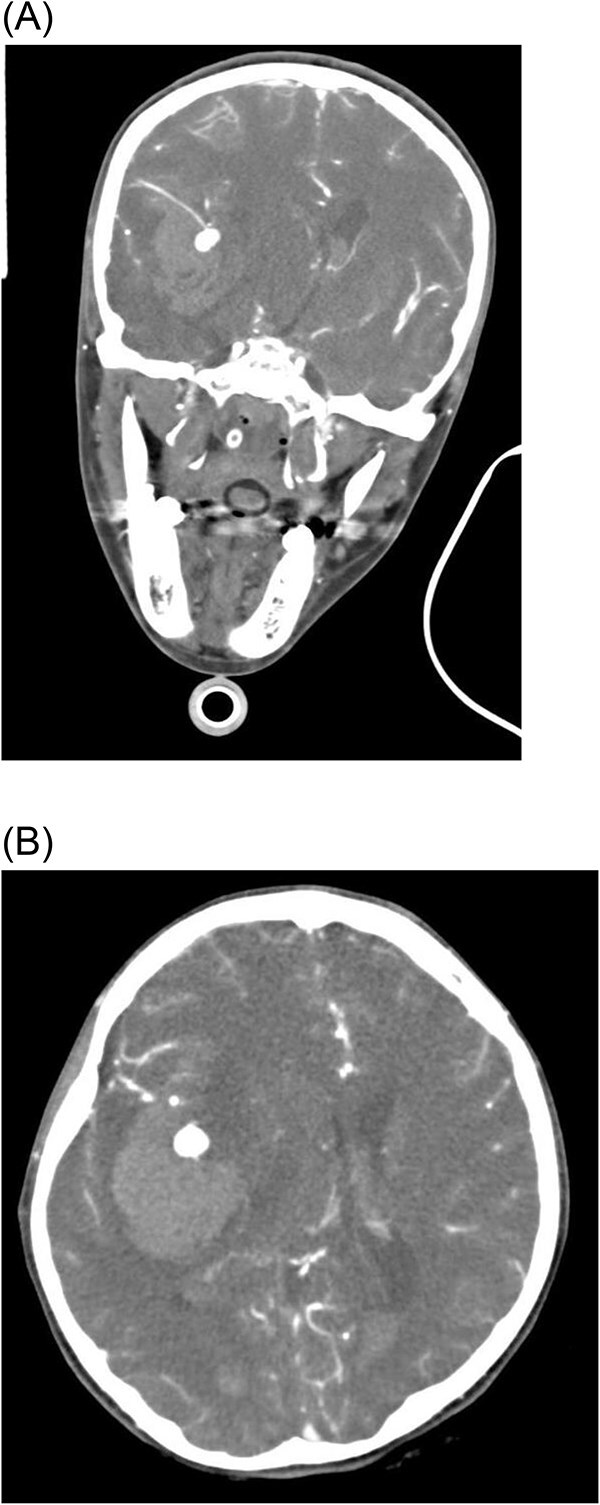

霉菌性动脉瘤(MAs)是感染性心内膜炎(IE)的一种罕见但危及生命的并发症,由感染性心内膜炎栓塞在脑血管内引起并导致动脉瘤形成。本病例报告描述了一名17岁女性在IE治疗期间出现多发性MAs,导致灾难性的神经功能衰退和最终死亡。在接受开胸手术切除植物后,患者因真菌性动脉瘤破裂出现颅内出血,在一次不成功的开颅减压手术后死亡。该病例强调了在IE背景下早期识别和及时干预MAs管理的重要性,以及需要制定方案来改善这些高危患者的预后。MAs破裂相关的高死亡率突出了这些并发症的严重性及其管理的挑战。

Mycotic aneurysms (MAs) are a rare but life-threatening complication of infective endocarditis (IE), resulting from septic emboli lodging in cerebral vessels and leading to aneurysm formation. This case report describes a 17-year-old female who developed multiple MAs during treatment for IE, resulting in catastrophic neurological decline and eventual death. After undergoing open-heart surgery for vegetation excision, our patient then developed intracranial bleeding due to mycotic aneurysms rupture, which led to her death after an unsuccessful decompressive craniotomy. This case highlights the importance of early recognition and timely intervention in the management of MAs in the context of IE, as well as the need for protocols to improve outcomes in these high-risk patients. The high mortality rate associated with ruptured MAs highlights the critical nature of these complications and the challenges in their management.